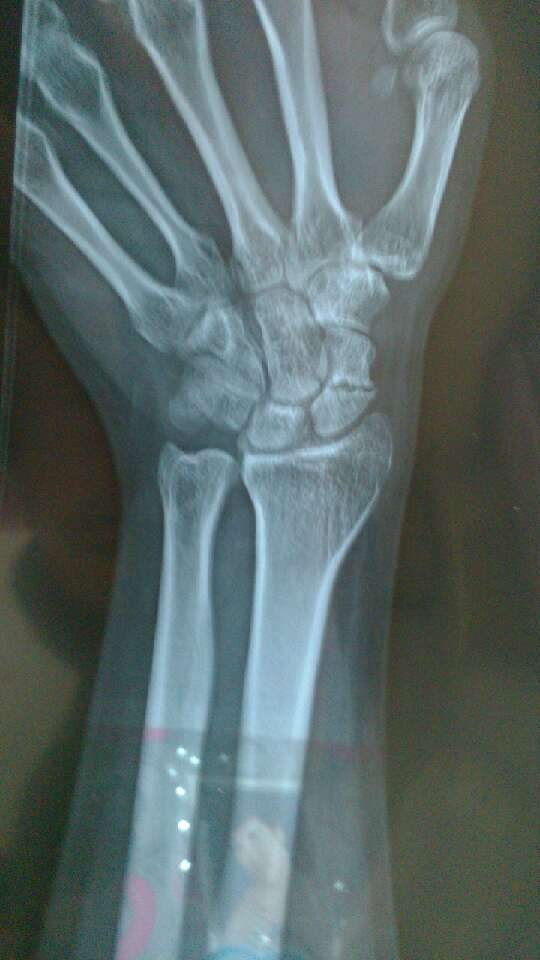

五个月前手腕扭伤 医生说很严重 必须手术 求高医看看 不手术,吃药能好吗? 点击展开 匿名用户 2013-07-03 12:03 为您推荐: 其他回答 估计不行,建议手续,避免以后留下hyz 匿名用户 2013-07-05 08:54 必须手术 呵呵 不要太在意 匿名用户 2013-07-05 00:21 相关问题 我手腕扭伤了怎么处理…用啥药… 医生您好!我的宝宝2岁20天~前一个星期得了喉炎打针吃药好了~可这几天又咳嗽的厉害~我去医院检查医 手腕扭伤有假如不治好啥后果?会自个好吗?我是正长…